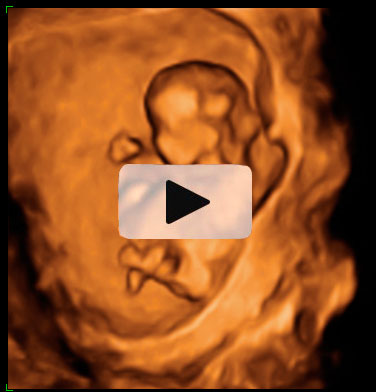

Ecografía 4D de la semana 12: Feto mirando "a la cámara"

Pueden observarse los huesos de la mano

Esta ecografía 4D muestra a un bebé de 12 semanas de gestación que se encuentra situado contra la pared del útero materno. El feto parece mirar varias veces hacia el ecógrafo y se tapa la cara con los brazos. Puede observarse con gran detalle la estructura ósea de la mano.

Ecografía en 4D de un feto de 12 semanas "mirando a la cámara"

A este niño de 12 semanas de gestación parece que le ha "pillado" el ecógrafo desprevenido y se quiere esconder. El bebé está contra la pared uterina: se da cuenta de que el ecografista le está "enfocando" y parece con si se quisiera esconder del público, como las estrellas de cine. Mira varias varias veces "a cámara", en una actitud sorprendente; se tapa la cara con los brazos. La mano se perfila perfectamente, así como muchas de sus estructuras óseas, mientras se esconde cara a la pared uterina.